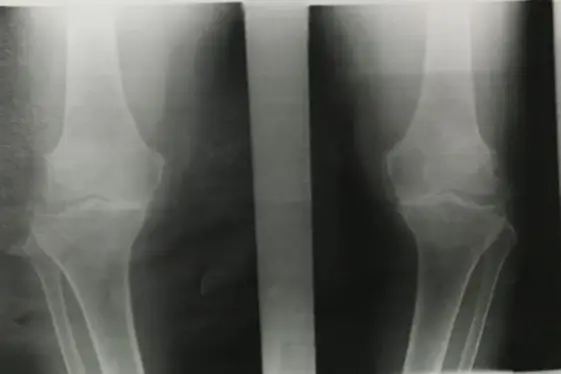

Examination of the knee

Knee Exam

https://www.youtube.com/watch?v=17ZKya9yR2Y

| Item | Procedure | Purpose/ Indication … | Attachment Links | Positive Finding/Interpretation |

| Look | Compare both limbs, Skin, Muscle bulk, bony landmarks, hair distribution | Assess symmetry, signs of trauma, inflammation, muscle atrophy, structural changes | Visual examples - Skin, Muscle, Bone, Joint: ![]() ![]() ![]() ![]() ![]() ![]() | Swelling, scars, discoloration, hair changes, muscle wasting, bony protrusions, angulation, redness |